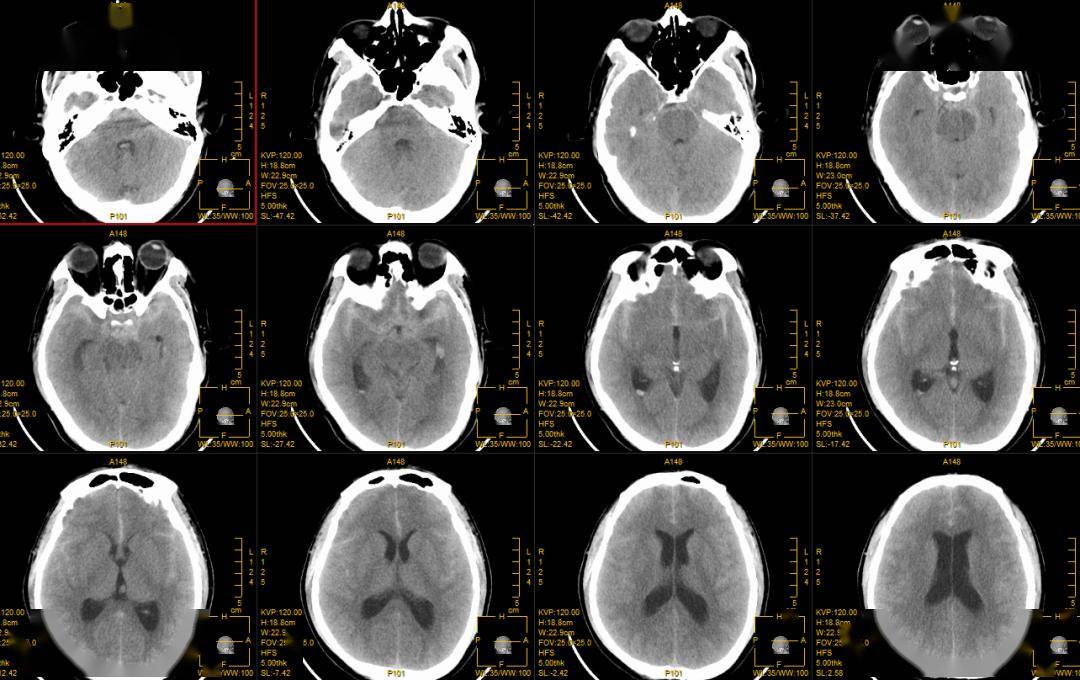

颅内动脉瘤ct图片

牛停芬,女,53岁,左侧大脑中动脉动脉瘤